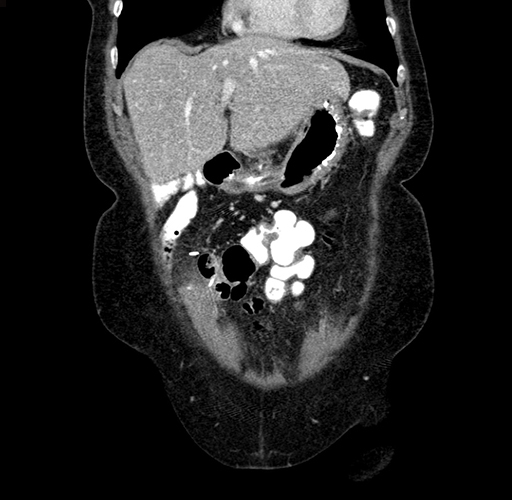

Pre-Chemo: Coronal Venous

Coronal Venous